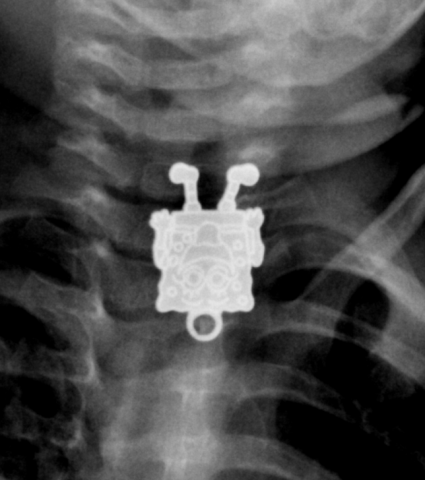

Ο κόσμος είναι ένα ενδιαφέρον μέρος, και τα νήπια (και τα μικρά παιδιά) τον ανακαλύπτουν εξερευνόντας τον, με όλες τους τις αισθήσεις ακόμα και την γεύση και την αφή. Είναι λοιπόν αναπόφευκτο να προσπαθήσουν να “δοκιμάσουν” οτιδήποτε βρίσκεται στο άμεσο οπτικό τους πεδίο. Για αυτόν τον λόγο, η πλειονότητα περιστατικών κατάποσης ξένου σώματος, αφορά ηλικίες 6μηνών – 6ετών και το 98% και περιλαμβάνει γνώριμα αντικείμενα όπως κέρματα, παιχνίδια, κοσμήματα, μπαταρίες και μαγνήτες

Σε πιο σοβαρές περιπτώσεις μπορεί να εμφανιστούν συμπτώματα όπως αίσθημα πνιγμονής, σιελόρροια, έμετος, δυσφαγία / άρνηση λήψης τροφής, συριγμός ή αναπνευστική δυσχέρεια. Για την εκτίμηση αυτών των περιστατικών, λαμβάνεται το κλινικό ιστορικό, καταγράφεται η ώρα κατάποσης, το είδος και μέγεθος του αντικειμένου ενώ ακολουθεί κλινική εξέταση και ανάλογα με το περιστατικό, ακτινολογικός έλεγχος (α/α θώρακος – κοιλιάς) για την εντόπισή του (αεροφόροι οδοί – οισοφάγος - στόμαχος)

Αν και ~65% των υλικών είναι ακτινοσκιερά, υπάρχουν αρκετά (π.χ. γυαλί – πλαστικό – ξύλο) τα οποία δεν “φαίνονται” στην ακτινογραφία , οπότε σε ισχυρή υποψία ή επί κλινικών συμπτωμάτων, είναι αναγκαία η περεταίρω εξέταση από ΩΡΛ ή η διενέργεια ενδοσκόπησης, και σπανιότερα άλλης απεικονιστικής εξέτασης

-Οι μικρές (στρογγυλές) μπαταρίες (λιθίου) πρέπει να αφαιρούνται άμεσα από τον οισοφάγο εξαιτίας της πιθανότητας ηλεκτρικού εγκαύματος του τοιχωματικού βλεννογόνου (κίνδυνος διάτρησης και μόλυνσης του μεσοθωρακίου). Εάν η μπαταρία εντοπίζεται στον στόμαχο, υπάρχει η πολυτέλεια αναμονής για 24-48 ώρες για αυτόματη κένωση, αν όμως δεν αποβληθεί στα κόπρανα μετά το πέρας του 48/ωρου, επιβάλλεται ενδοσκοπική αφαίρεση.

-Οι μικροί μαγνήτες είναι ακόμα ένα επικίνδυνο υλικό. Εάν το παιδί καταπιεί δύο ή περισσότερους ή εάν καταπιεί ένα μαγνήτη και ένα μεταλλικό αντικείμενο, αυξάνει ο κίνδυνος επιπλοκών (απόφραξης ή ρήξης) και επιβάλλεται η άμεση αφαίρεσή τους (ενδοσκοπικά εάν είναι στο στόμαχο ή χειρουργικά εάν στο έντερο)